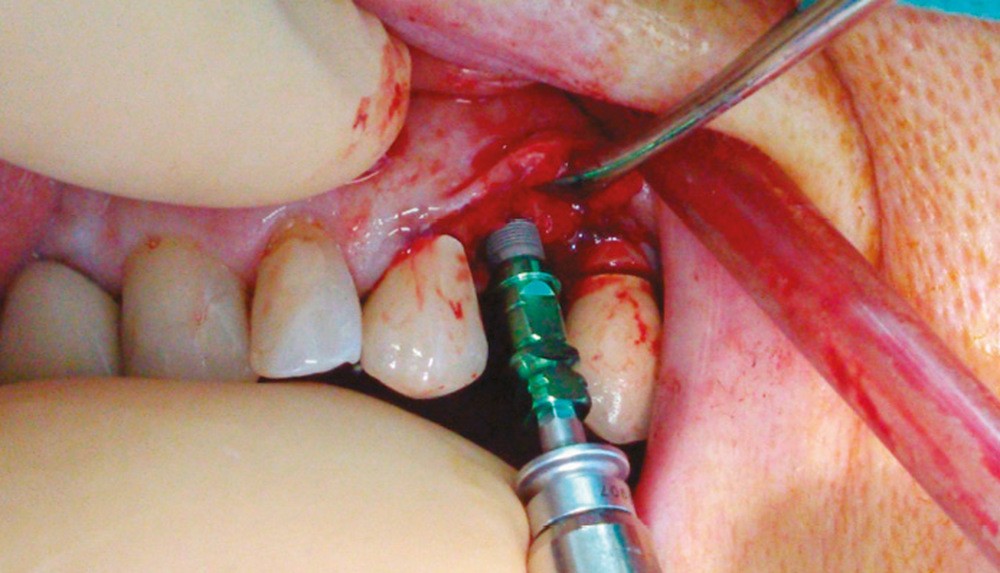

Un contrôle à la fréquence de 4 à 6 mois devra être instauré. La fréquence sera adaptée à l’état bucco-dentaire et à l’appréciation des facteurs locaux de susceptibilité du patient (risque carieux, biotype parodontal). La motivation à l’hygiène et l’efficacité du contrôle de plaque devront être entretenues. Les soins conservateurs précoces seront bien entendu privilégiés. Dans ce contexte, il ne faudra pas hésiter à conserver des dents d’une valeur intrinsèque faible pour éviter le recours à un geste chirurgical. En cas de carie délabrante ou de mobilité modérée, les soins conservateurs devront être privilégiés (endodontie, contentions). En cas d’infection, un traitement conservateur devra également être envisagé (fig. 2).

La priorité devra être donnée à la suppression de la composante infectieuse. Ainsi, pour éviter une extraction, il pourra être légitime de préconiser la conservation d’une dent à l’état de racine sur laquelle le traitement endodontique aura permis la stérilisation du foyer infectieux. Cependant, ce traitement conservateur ne sera retenu qu’à condition de pouvoir conserver durablement cette racine par une obturation étanche à l’aide d’un matériau de reconstitution définitif. Toutefois, pour contrôler l’infection, l’extraction pourra être nécessaire d’emblée ou en cas d’échec d’un traitement conservateur.